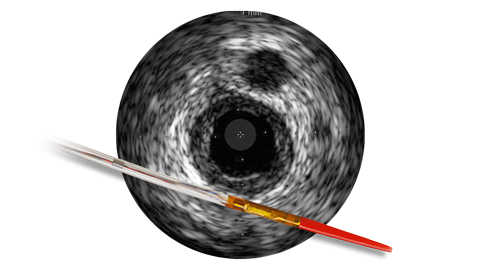

IVUS guidance was associated with less contrast: 20 ml vs. 64.5 ml, p<.001, n=83 patients randomized to IVUS or angiographyguided PCI.12 IVUS may help to determine: • Pathology at the ambiguous site to optimize your treatment strategy • Device utilization without additional radiation and contrast